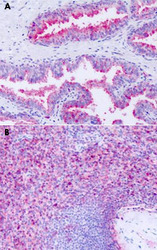

PAB26028 IHC

Full details

Method:

Other validation